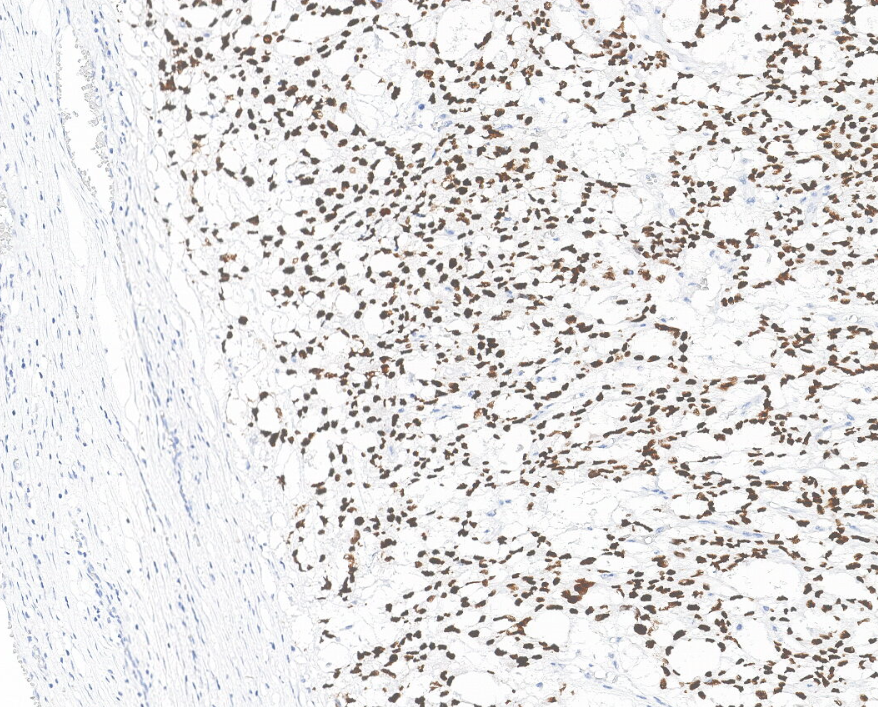

Localisation : Noyau

Son expression nucléaire est devenue un marqueur standard pour ces tumeurs.

Contrôle positif : Tissu de séminome